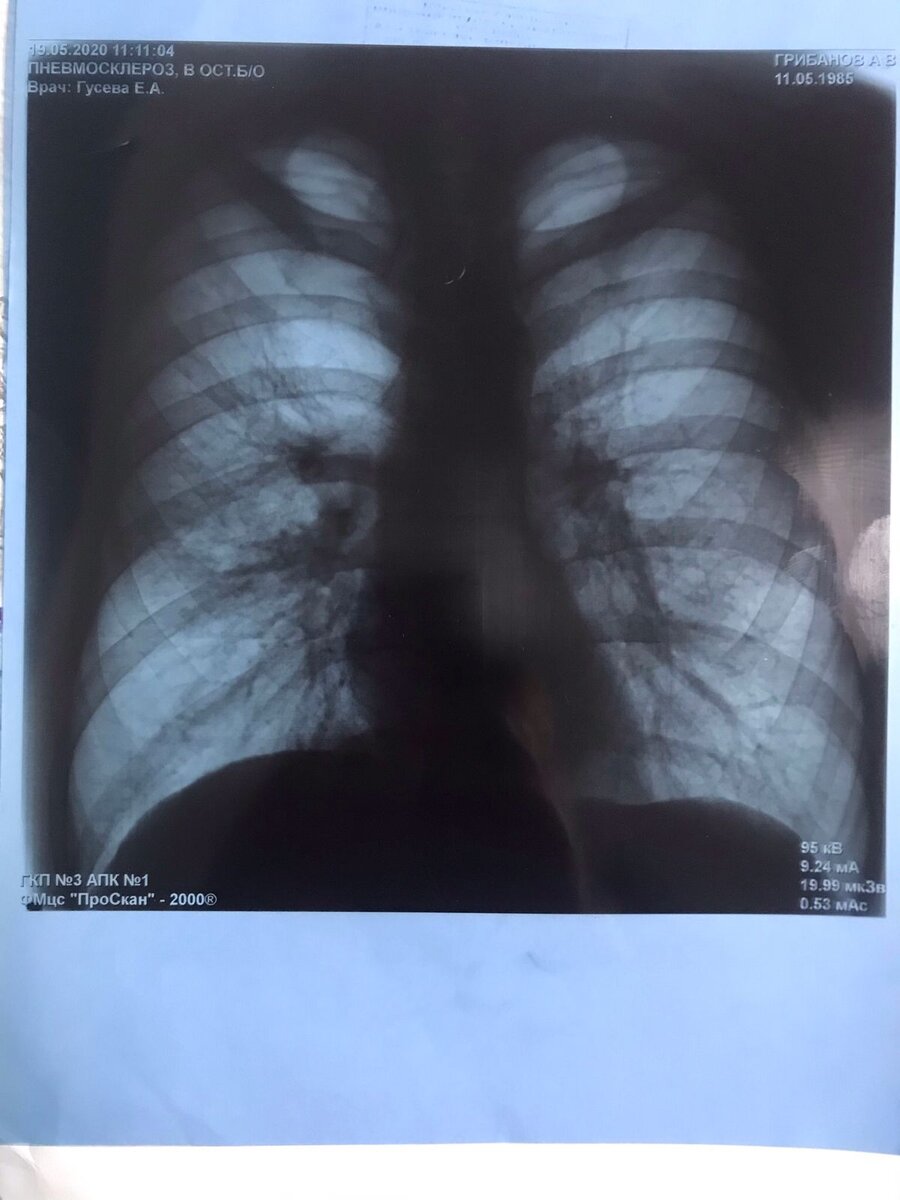

Мой снимок за пол года до обнаружения туберкулеза. Врачи говорят что на нем все хорошо... может найдется читатель, который скажет обратное... милости прошу в комментарии.